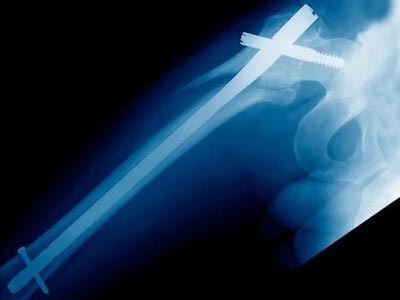

Face à une demande croissante, nous avons depuis 2009 très largement renforcé notre activité médicale.

L'étroite collaboration entretenue avec nos partenaires ainsi que la maitrise des exigences de ce secteur (Normes, Matériaux...) nous permettent aujourd'hui de développer des dispositifs innovants.